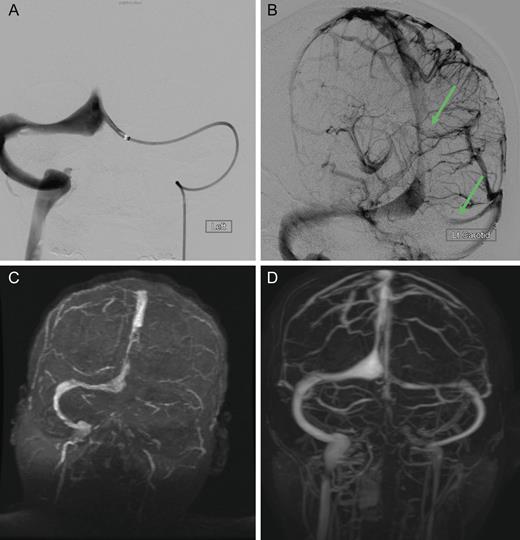

Dural sinus venogram (A) Prior to endovascular mechanical thrombectomy (B) Post mechanical thrombectomy. (C) Pre-intervention MRV demonstrating complete occlusion of the left transverse sinus and near occlusion of the posterior portion of the superior sagittal sinus. (D) Post-intervention MRV demonstrating persistent recanalization of the left transverse and sigmoid sinuses, along with much improved flow in the posterior superior sagittal sinus. Note the recanalization of the left transverse sinus and the much improved flow in the superior sagittal sinus.

The patient was treated emergently with endovascular mechanical thrombolysis with technical success (Fig. 3A and B), followed by systemic anticoagulation therapy. Post-intervention MRV demonstrated persistent recanalization of the left transverse and sigmoid sinuses, along with much improved flow in the posterior superior sagittal sinus (Fig. 3D).

Cranial computed tomography (CT) demonstrated subtle hypodensity mainly in the left occipital lobe, with a characteristic empty delta sign (Fig. 1). Computed tomography angiography demonstrated normal filling of the posterior cerebral arteries (PCA). Cranial magnetic resonance imaging (MRI) evaluations demonstrated bilateral ischemic changes involving the occipital and parietal lobes, more extensively on the left (Fig. 2). Magnetic resonance venography (MRV) demonstrated complete occlusion of the left transverse and sigmoid sinuses, as well as near occlusion of the posterior superior sagittal sinus (Fig. 3C).